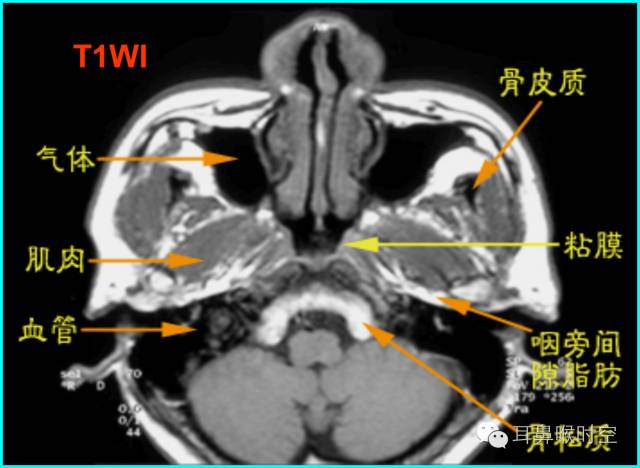

MRI

采用SE 序列矢状面T1WI

选择正中矢状面,分别测量两条径线(图1、2)

N 线:即从蝶骨体2枕骨斜坡的软骨结合部后缘(O点)至硬腭与软腭上缘交界处的连线N

A 线:过O点沿枕骨斜坡下缘作延长线L,取腺样体下缘最凸点作L线的垂直线。

A/N比:分别测A、N值,计算A/N 比

解剖结构:在MRSET1WI 鼻咽部正中矢状面图像上,由于采取薄层断面成像

可以直观显示腺样体本身

清晰显示蝶骨体与枕骨斜坡之间的软骨接合部、鼻后孔间隙、鼻甲、硬腭与软腭上缘的交界面、软腭、会厌软骨等结构

易于测量:非常容易画出A 线及N 线,及测量PAS,了解鼻后孔间隙、鼻甲大小、软腭厚度及后突程度

动态观察:利用MR电影可动态观察鼻咽部随呼吸运动的情况,大大丰富了诊断信息。

任意平面:MR扫描不受体位影响,可行任角度断面扫描与图像重建,从而保证其正中矢状面图像的质量

可重复性:MR是一种无创性检查,无X线辐射危害,不影响儿童生长发育和健康。

MRI表现:

多方位检查

有利于显示肥大的腺样体

呈等T1、长T2信号

增强时可强化